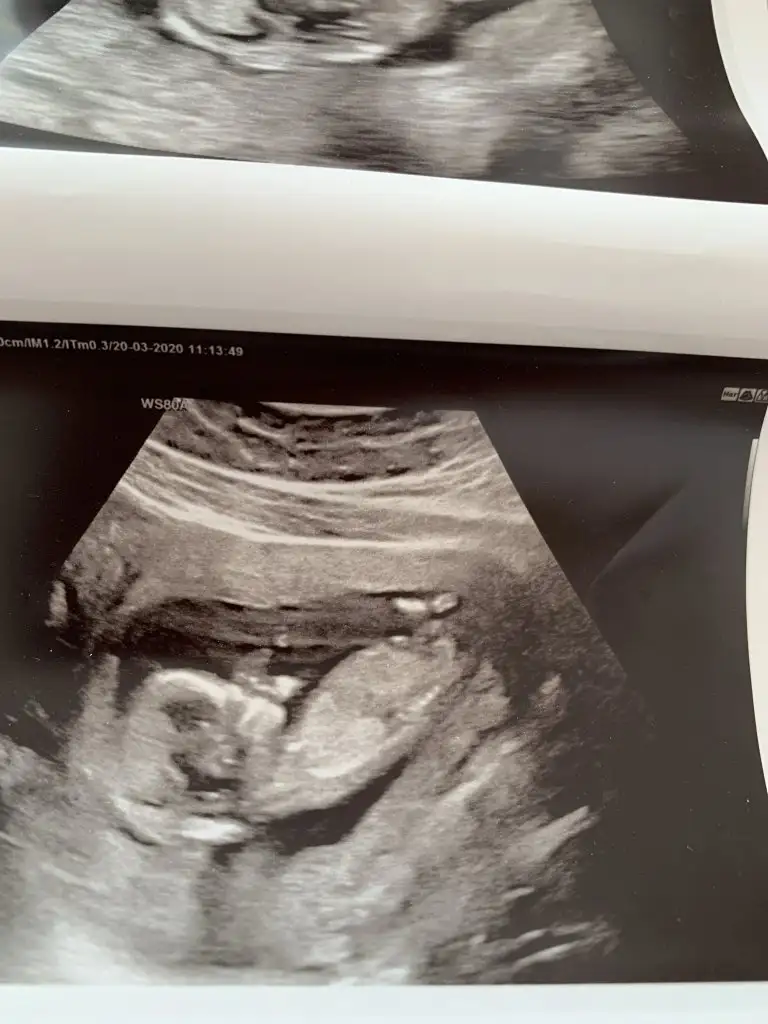

Ben de atıyorum o zaman hemen 13. Hafta sayfada bir doktor arkadaş yorum yaptı ama buraya da atayım dedim :)

Kim yorum yaptı anlamadım 😊 burada nubu kız gibi gibi ne dik nede paralel ama oyumu kız kullanıyorum başka usg de paylaşın 😊